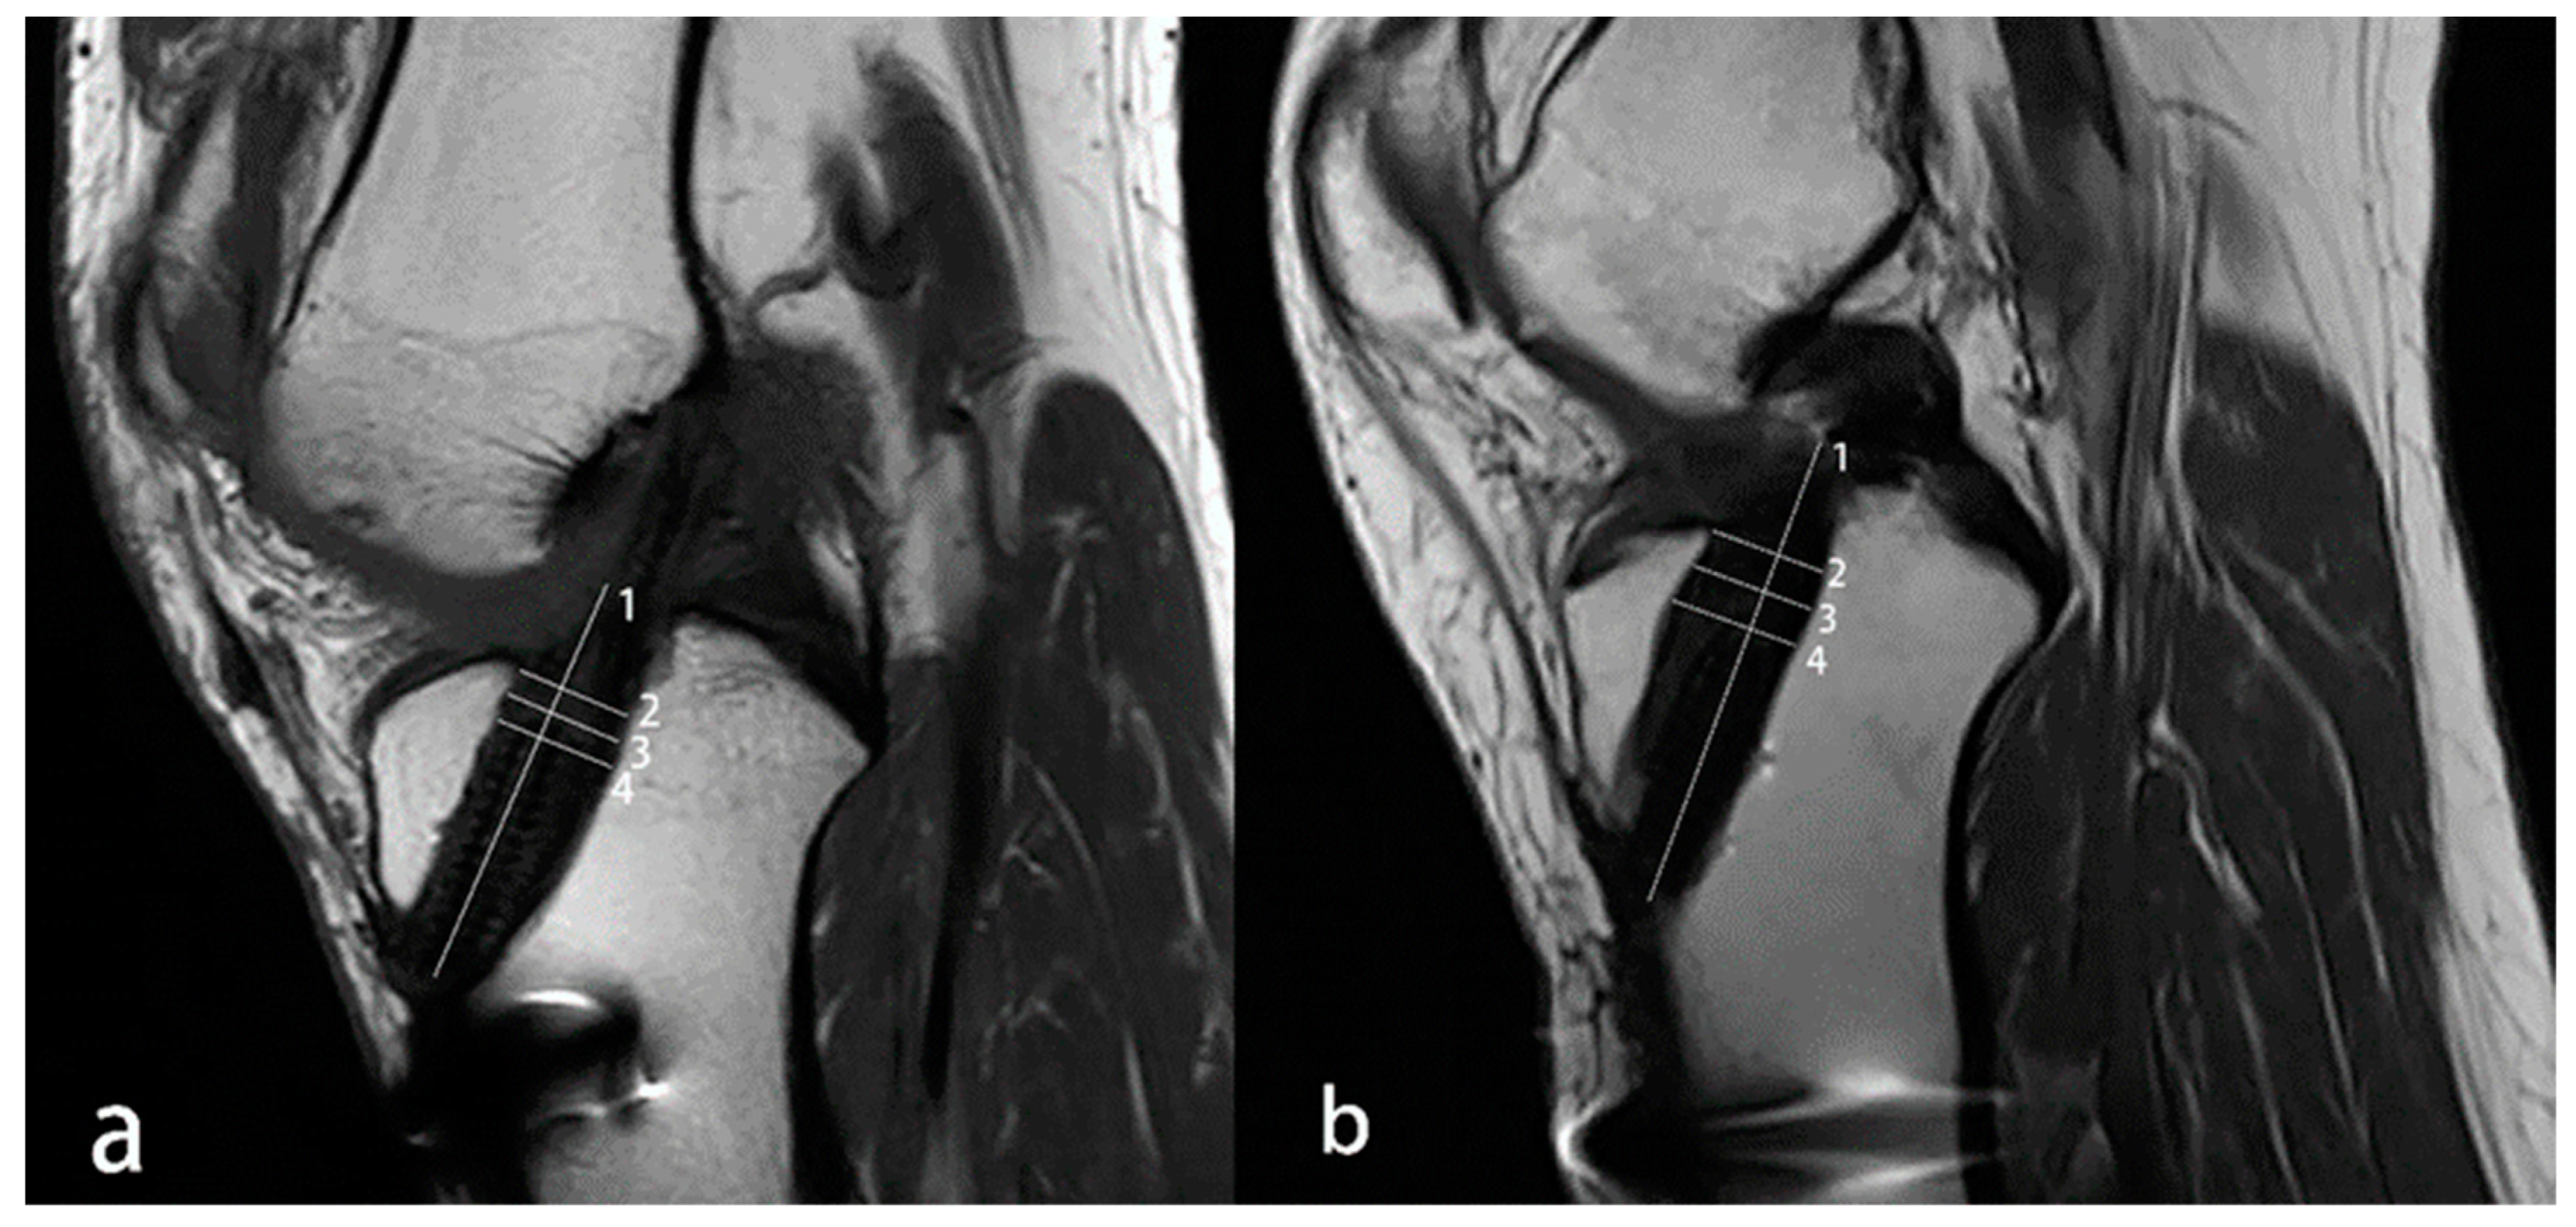

| Cutting Levels | Interobserver | Intraobserver | |

|---|---|---|---|

| 1 | 2 | ||

| joint line level | 0.897 | 0.922 | 0.891 |

| center level | 0.881 | 0.870 | 0.883 |

| screw top level | 0.898 | 0.919 | 0.926 |